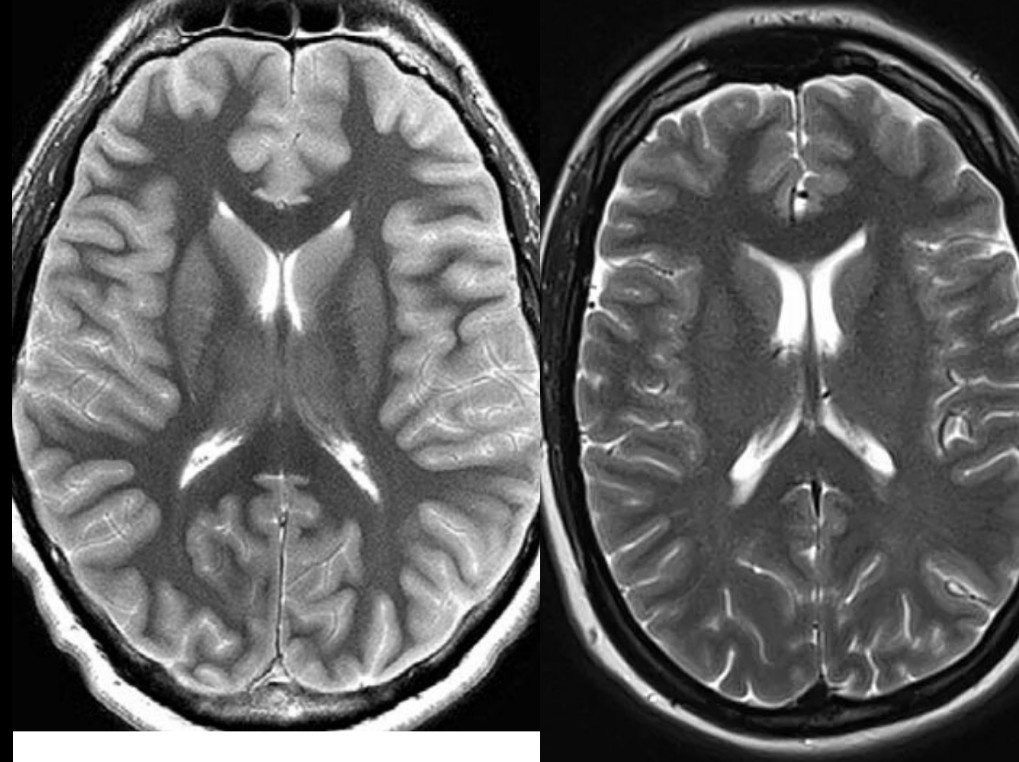

• Повышение интенсивности сигнала от коры мозга:

Сравнение коры мозга на МРТ Т2-ВИ живого человека (справа) и человека после перенесенной клинической смерти на первые сутки (слева). Кроме повышения сигнала от коры отмечается сужение боковых желудочков мозга и его борозд, обусловленное отеком.